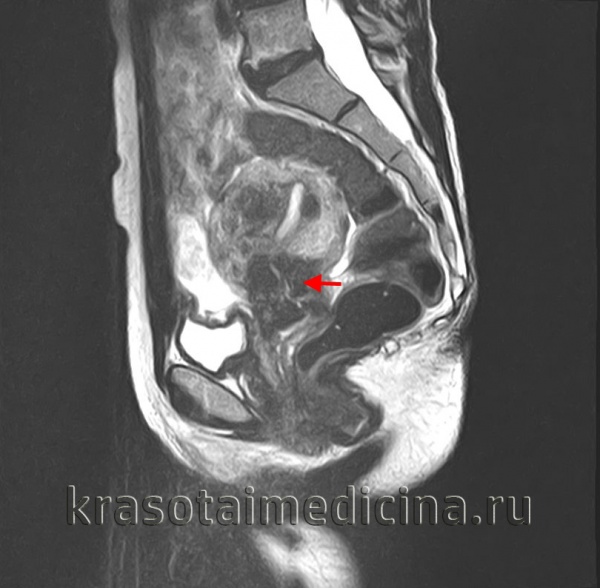

- Магнитно-резонансной томография (МРТ) органов малого таза; (рис 4.)

Рис. 4 МР-признаки опухоли шейки матки

Данные выполненных исследований позволяют установить стадию рака шейки матки и определить индивидуальную тактику лечения.